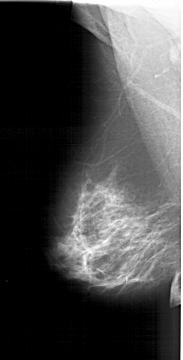

A_1382_1.LEFT_MLO

LEFT_MLO LINES 6106 PIXELS_PER_LINE 3106 BITS_PER_PIXEL 12 RESOLUTION 43.5 NON_OVERLAY